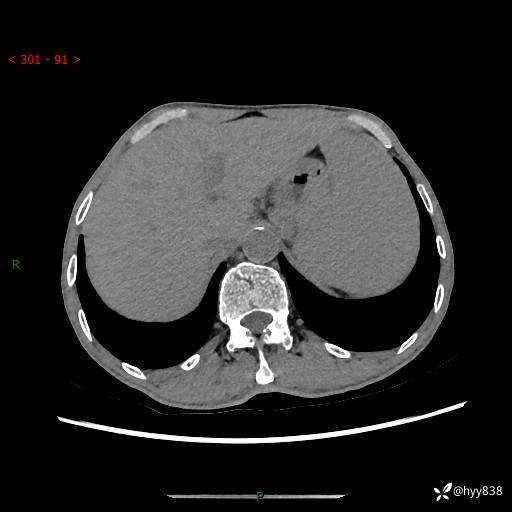

老年男性,脾大并脾脏弥漫粟粒状低密度,淋巴瘤 VS 肉芽肿 VS 血管瘤---结果公布

简要病史: 患者于3月前无明显诱因出现脾大,伴腹部轻微不适,具体不详,无腹痛、腹泻、腹胀,无头晕、头痛、乏力,无恶心、呕吐、呕血,无胸闷、气短、胸痛不适

上腹部CT平扫+增强